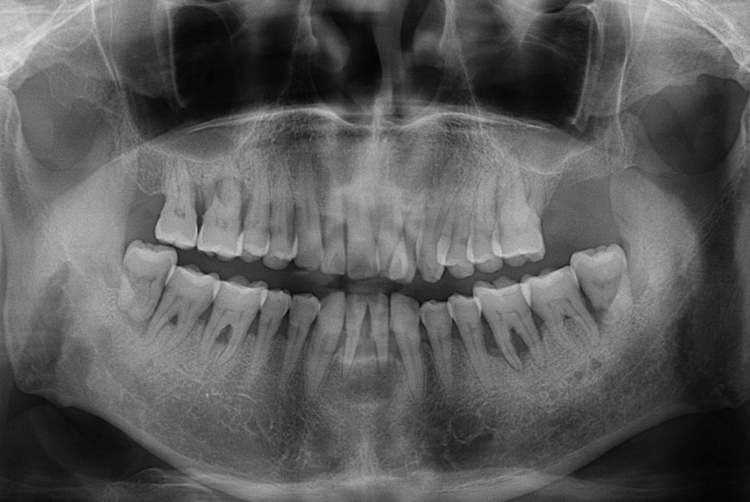

[임플란트] 어금니 임플란트

치료후 : 2016-04-22

세종치과는 많은 환자와 다양한 케이스를 바탕으로

항상 편안한 임플란트 수술을 제공하고자 노력하고,

오래동안 튼튼히 쓸 수 있는 임플란트 수술을 가장 큰 목표로 삼고 있습니다.